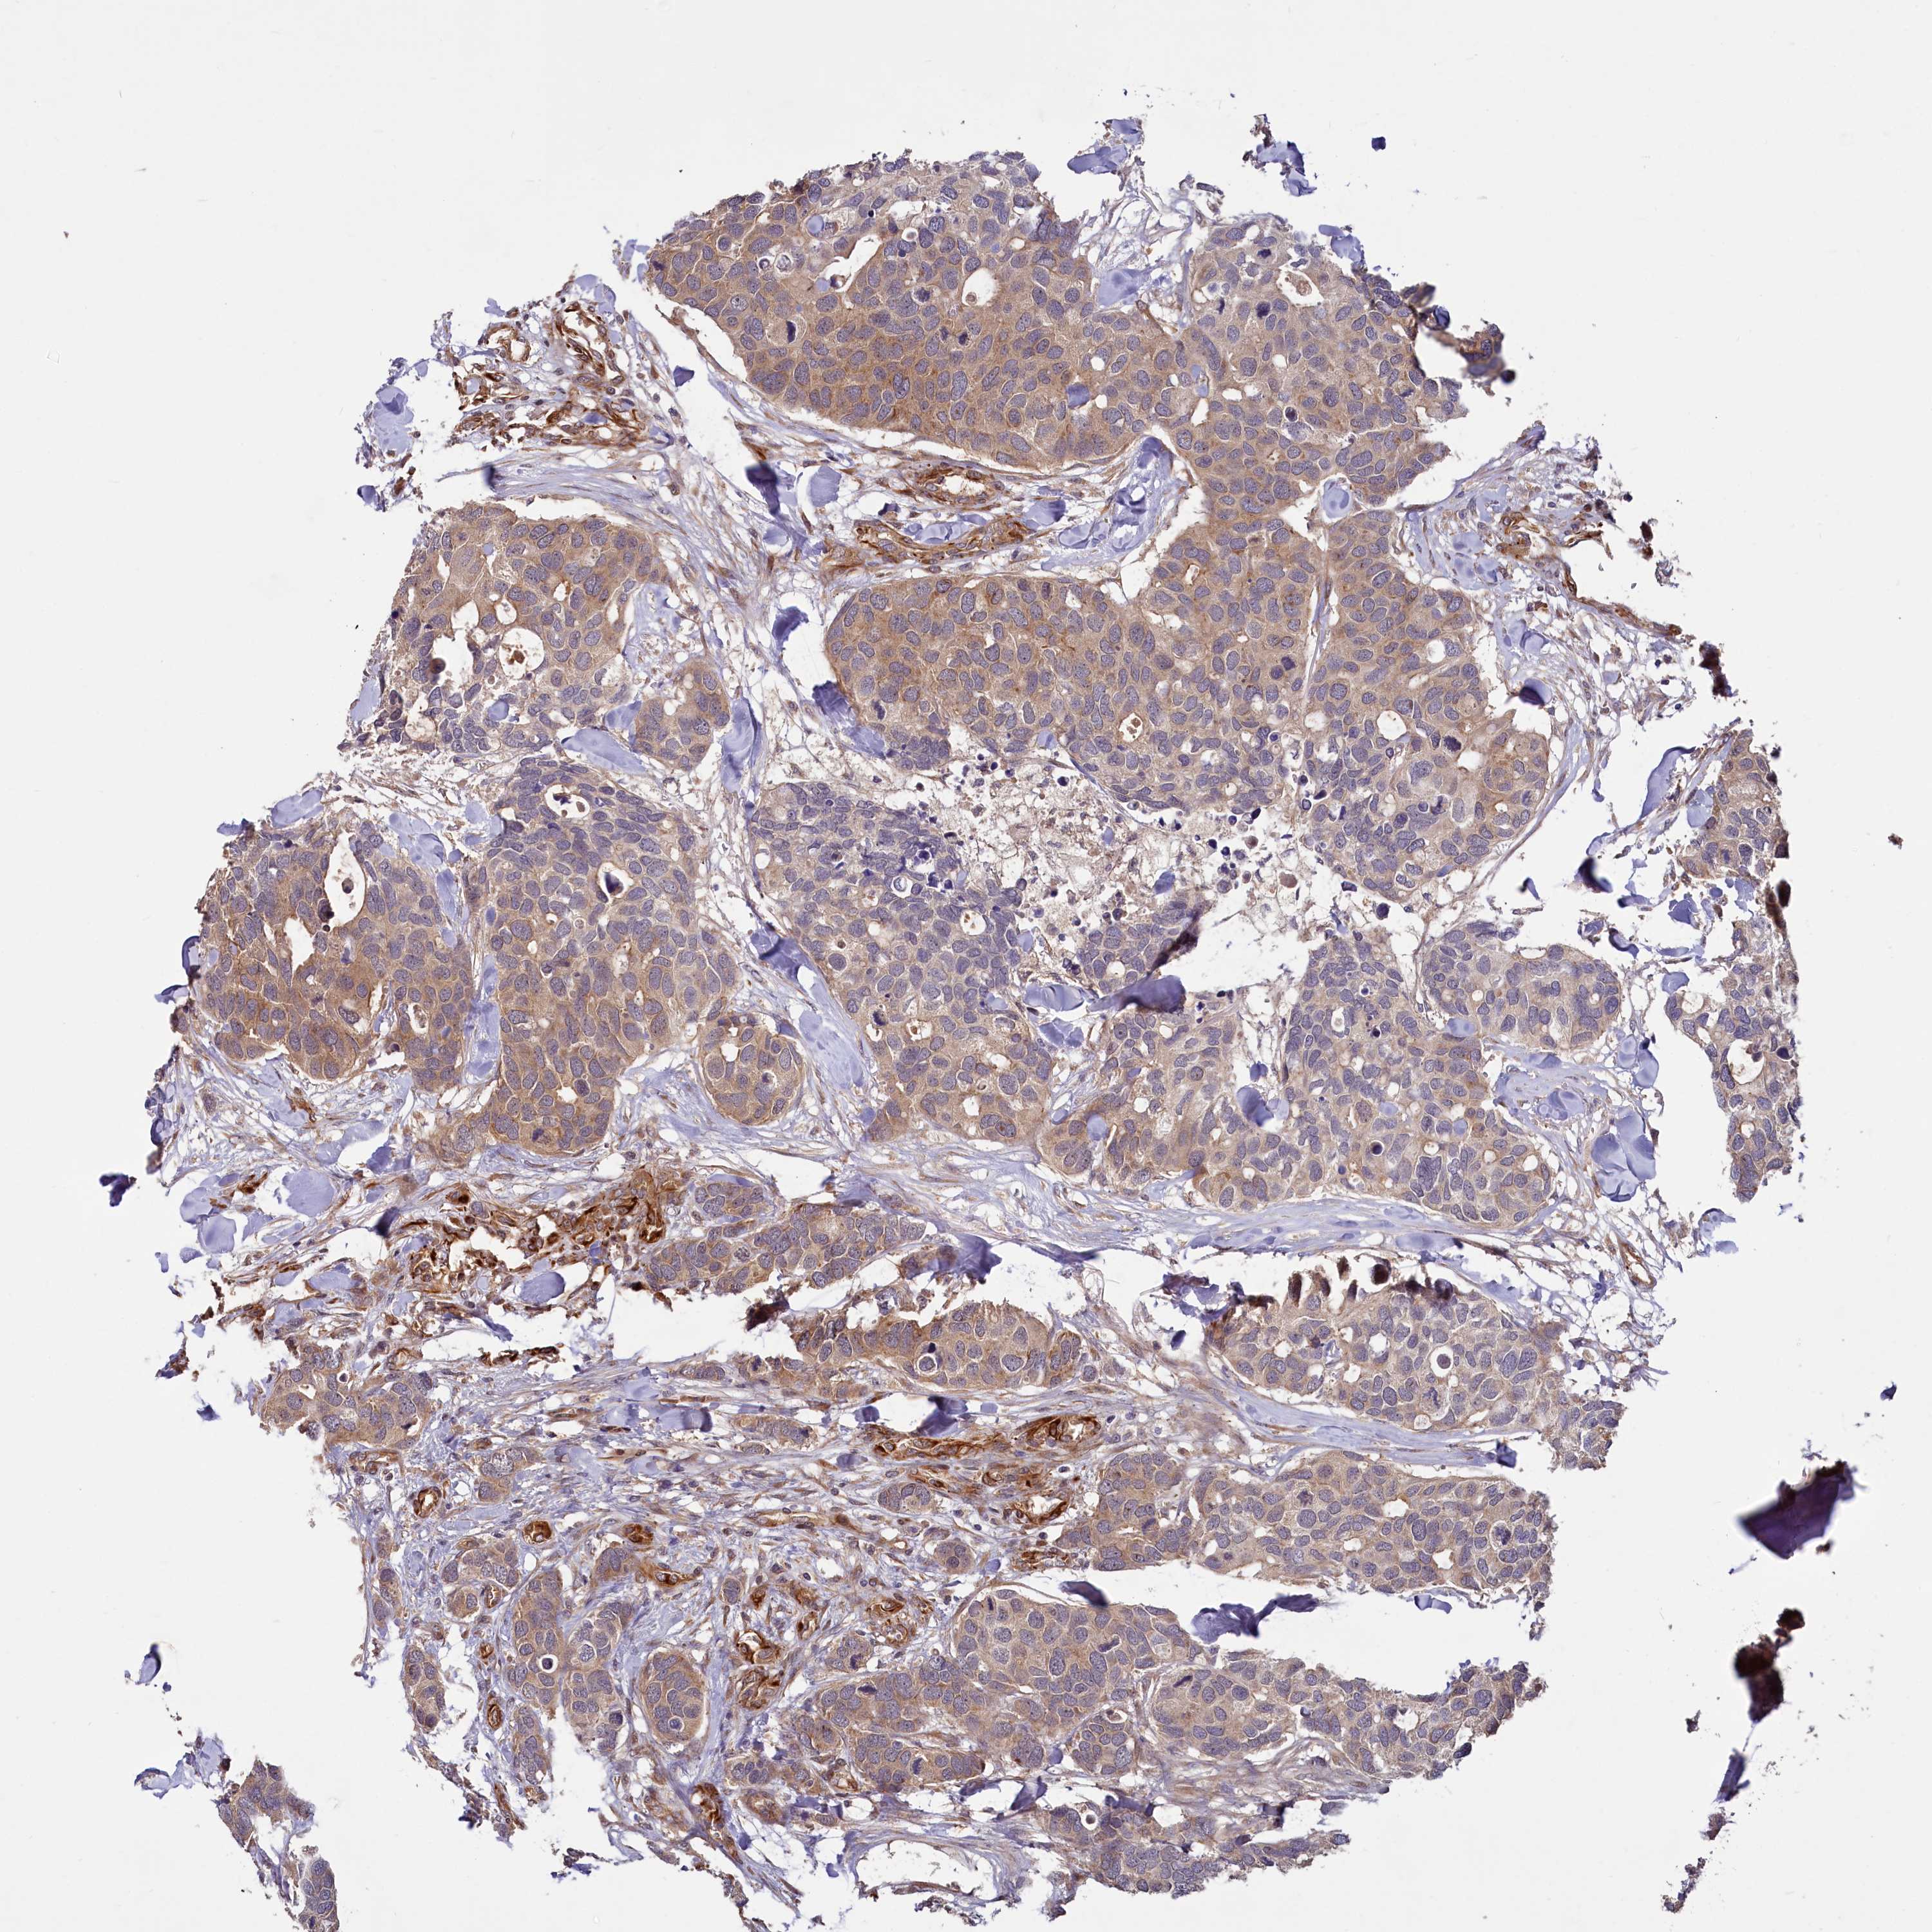

BRCA TCGA BRCA VALIDATION PROTEIN EXPRESSION

ANTIBODIES

AND

VALIDATION